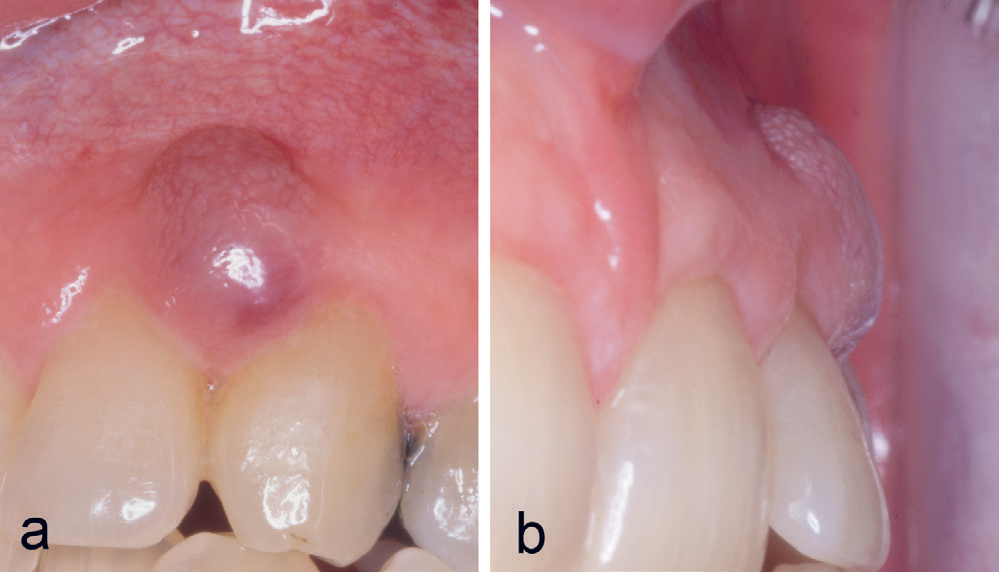

Kasus 3

En ni år gammel gutt ble henvist fra sin tannlege for fjerning av hemangiom. Ved klinisk undersøkelse var der en hevelse buccalt for tann 12. Den var blå-rød av farge og var fastere enn et hemangiom vanligvis er. Den dekket halve kronen buccalt ved 12 (figur 3a, b), og det var ikke noen patologiske forandringer å se på røntgen (figur 3c). Lesjonen ble fjernet og benoverflaten dekket med salveveke. Den kliniske diagnosen PKCG ble bekreftet histologisk. Det ble sekundær epitelialisering, og kontroll seks måneder postoperativt viste intet residiv.

Figur 3. Kasus 3. PKCG buccalt for 12 hos en ni år gammel gutt (a, b). Røntgen (c) viste ingen patologiske forandringer.

Kasus 9

En 42-årig mann var henvist fra egen tannlege for fjerning av tumor buccalt regio 22–23. Pasienten hadde hatt en langsomt voksende tumor de siste seks månedene. Undersøkelse viste en blålig hevelse (figur 7a, b), og den kliniske diagnosen PKCG ble bekreftet histologisk. Ved kontroller tre og seks måneder postoperativt ble det ikke funnet residiv.

Figur 7. Kasus 9. PKCG (a, b) hos en 42-årig mann.